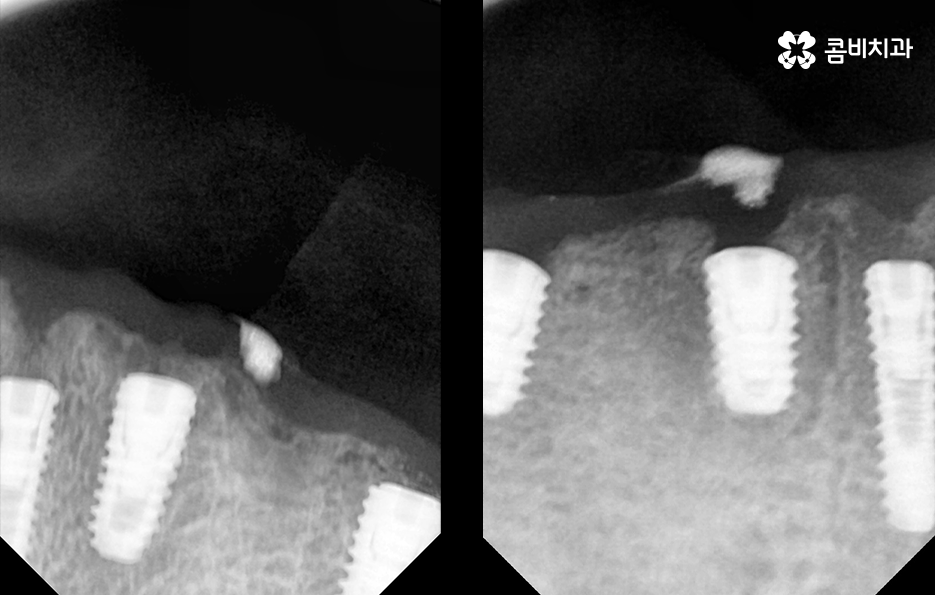

하지만 노년층의 환자분들의 경우 경제적인 부분이 부담스럽거나 치아를 잃은 개수만큼 임플란트를 식립하고 싶어도 잇몸 상태가 너무 좋지 않은 경우에는 임플란트 식립을 해야 하는 개수를 줄이고 치아의 머리부분을 연결하는 브릿지 형태로 임플란트 시술을 진행하는 경우가 있는데요

전체임플란트 해야 하는 상황에서 가장 권장하는 방법은 치아를 잃은 개수만큼 임플란트를 식립하는 방법이 되겠지만 그다음으로 잇몸 상태나 경제적 상황 등을 고려할 때 선택할 수 있는 방법 중 하나는 임플란트 브릿지를 활용한 치료 방법이라 할 수 있어요

임플란트 브릿지를 활용하여 전체임플란트를 하는 경우 보통 임플란트를 6~8개 정도 식립을 한 후에 임플란트의 머리부분을 연결하여 힘을 분산시키는 방법으로 저작력을 유지시키고 있어요